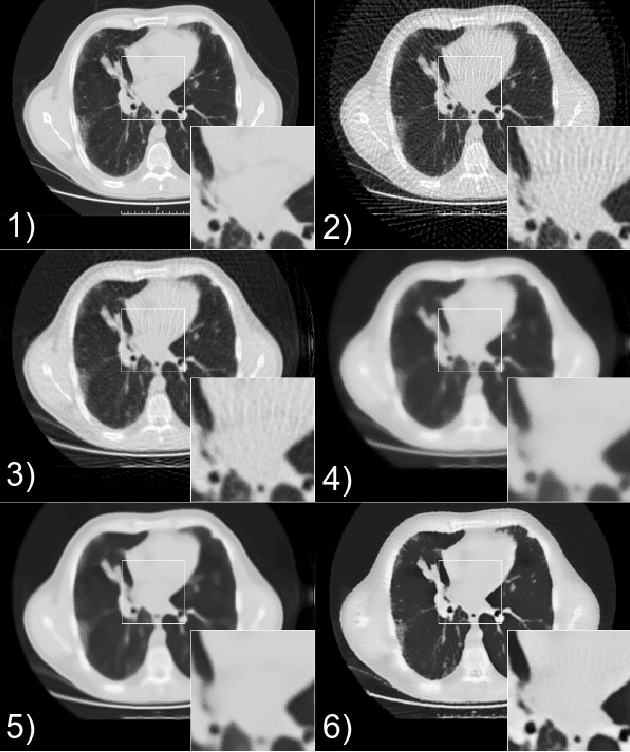

Abstract:Although Total Variation (TV) performs well in noise reduction and edge preservation on images, its dependence on the lambda parameter limits its efficiency and makes it difficult to use effectively. In this study, we present a Learnable Total Variation (LTV) framework that couples an unrolled TV solver with a data-driven Lambda Mapping Network (LambdaNet) predicting a per-pixel regularization map. The pipeline is trained end-to-end so that reconstruction and regularization are optimized jointly, yielding spatially adaptive smoothing: strong in homogeneous regions, relaxed near anatomical boundaries. Experiments on the DeepLesion dataset, using a realistic noise model adapted from the LoDoPaB-CT methodology, show consistent gains over classical TV and FBP+U-Net: +2.9 dB PSNR and +6% SSIM on average. LTV provides an interpretable alternative to black-box CNNs and a basis for 3D and data-consistency-driven reconstruction.